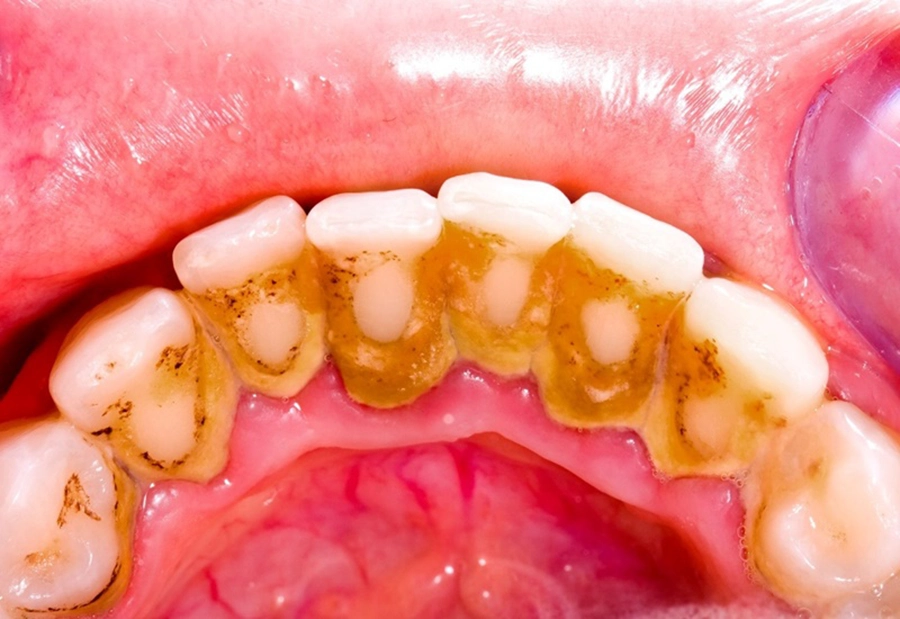

4.1 Mảng bám và cao răng tích tụ lâu ngày

Nguyên nhân hàng đầu dẫn đến viêm nha chu là mảng bám – lớp màng vi khuẩn mỏng hình thành liên tục trên bề mặt răng sau mỗi bữa ăn. Nếu không được làm sạch đúng cách, mảng bám sẽ cứng lại thành cao răng, bám chặt vào thân và chân răng.

Cao răng là nơi trú ngụ lý tưởng cho vi khuẩn sinh sôi. Khi vi khuẩn phát triển mạnh, chúng tiết ra độc tố gây viêm nhiễm, phá hủy mô nướu và dây chằng quanh răng. Đây chính là lý do tại sao những người ít đi lấy cao răng định kỳ thường có nguy cơ cao mắc bệnh nha chu.

Điều đáng lo ngại là cao răng không thể loại bỏ bằng bàn chải thường. Người bệnh cần đến nha khoa để được lấy cao răng bằng dụng cụ chuyên dụng nhằm loại bỏ ổ vi khuẩn tận gốc.